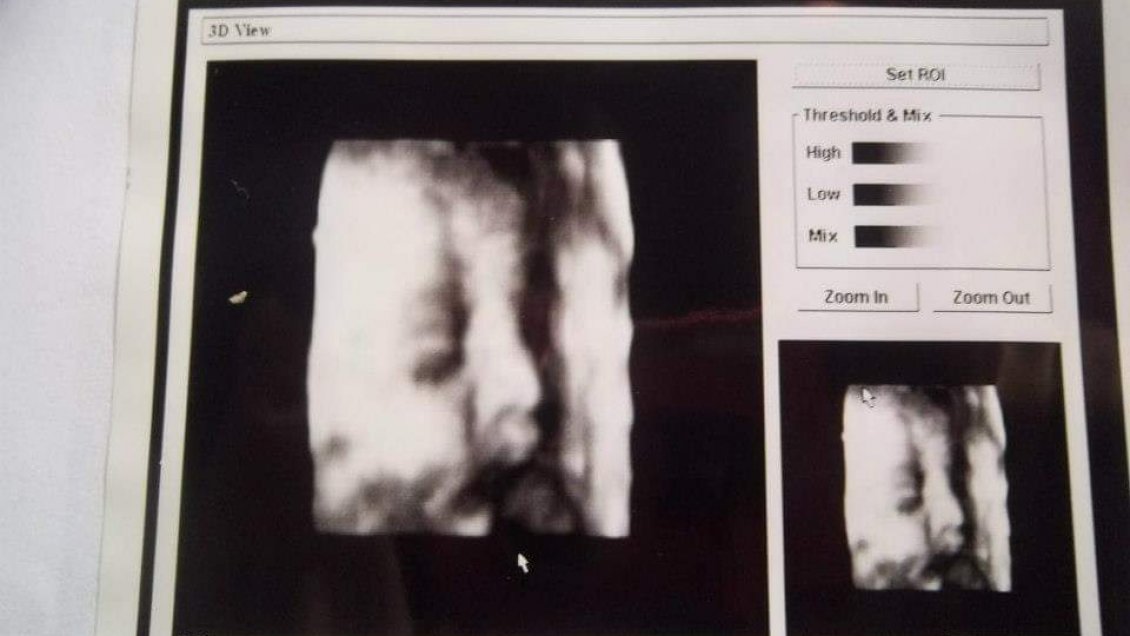

La imagen del feto que utilizaba el doctor Oliva.